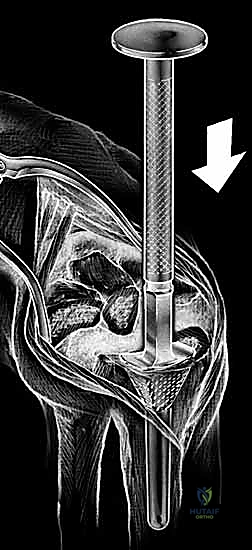

6. تثبيت المفصل الصناعي النهائي

يتكون المفصل الصناعي من جزأين رئيسيين: الجذع الكعبري (الذي يُزرع في عظمة الكعبرة في الساعد) والجذع الرسغي (الذي يُزرع في عظمة المشط الثالثة في اليد). يتم تثبيت هذه الأجزاء إما باستخدام الإسمنت العظمي الطبي، أو عن طريق الانحشار الميكانيكي الدقيق (Press-fit) الذي يسمح بنمو العظم داخل المفصل الصناعي. بين هذين الجزأين المعدنيين، توضع قطعة بلاستيكية عالية الجودة تعمل كغضروف صناعي يسمح بالحركة السلسة.